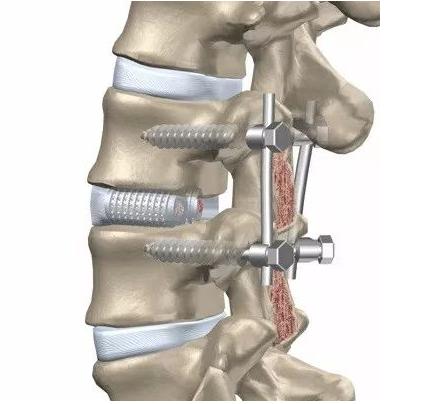

做脊柱手术,我们放进体内的这种内置物,大家通常所说的“板子”、“螺钉”或者“钉棒系统”,要不要取出是视情况而定的。

打钉子、做固定,固定和融合其实是两种不同的术式。虽然我们常常在固定的同时也做了融合,但也有部分病人我们只做固定,不做融合。比方说,有一部分胸腰椎的骨折,我们只做固定,为骨折愈合创造一个条件,将来等到骨折愈合之后,这个钉子可以去掉。

绝大多数的内固定物,就是我们说的“钉子”,目前绝大部分都是钛合金的,钛合金本身的组织相容性特别好,它对机体的影响非常小,所以就算钉子不取,对机体也没有明显影响。所以对于椎体间进行了融合的患者,大多数情况下,不建议取内固定。